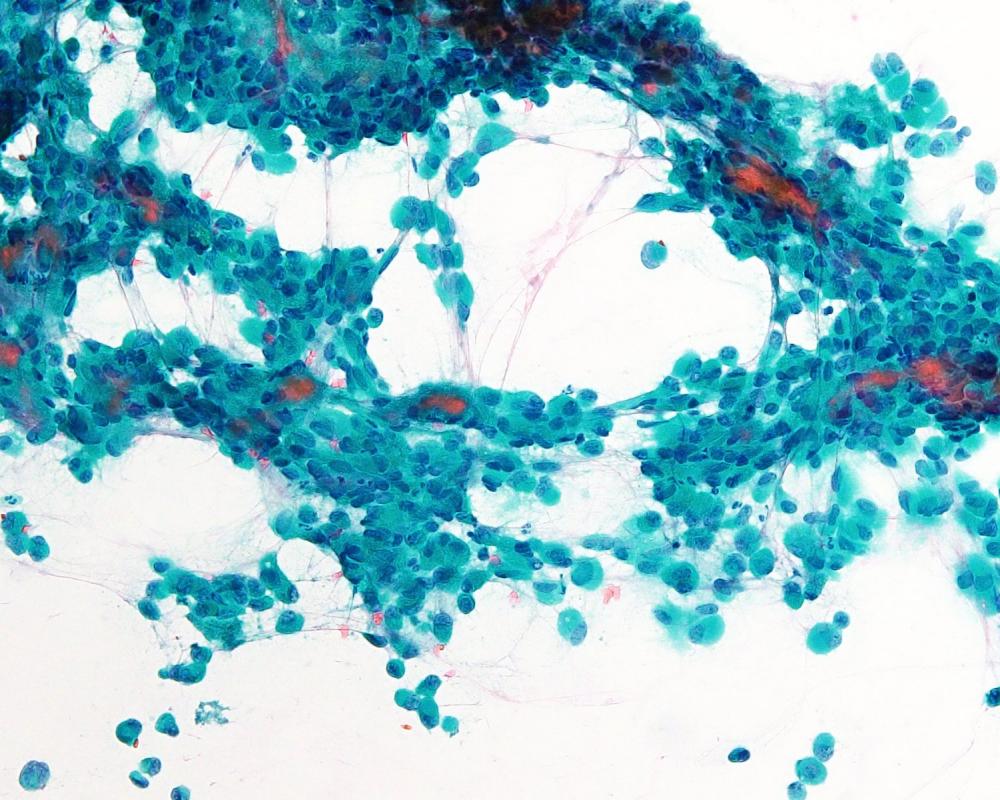

第40回日本臨床細胞学会九州連合会学会(大分)スライドカンファレンス症例1

種別:婦人科

出題:橋口 真理子 佐賀大学医学部病因病態科学講座

| 年齢 | 10代 | 性別 | 女性 |

| 採取部位 | 右卵巣腫瘍 | 採取方法 | 捺印細胞診 |

既往歴 特になし

妊娠出産歴 未経妊未経産

現病歴 手術の2か月前頃から腹部膨満感を自覚し近医受診。腹部エコーで骨盤内に17㎝大の充実性腫瘤を指摘され当院受診。右側卵巣腫瘍の診断で手術が施行された。右付属器切除術が行われ、術中迅速に提出された。右卵巣は20㎝程度に腫大し、割面は黄白色調で充実性腫瘤であった。捺印細胞診を採取した。

術前の採血では、hCG329mIU/ml (1.0 以下)、AFP3.3ng/ml(0~7.0)、CA125 92 U/ml (0-35)、LDH 2772U/L (124-222)であった。

| 正解 | 2.Dysgerminoma |

▼選択肢及び投票結果

| 1.Yolk sac tumor | 17件 | (16.2%) | |

| 2.Dysgerminoma | 77件 | (73.3%) | |

| 3.Granulosa cell tumor | 2件 | (1.9%) | |

| 4.Clear cell carcinoma | 7件 | (6.7%) | |

| 5.Neuroendocrine carcinoma | 2件 | (1.9%) | |

| 投票総数 | 105件 | (100%) |